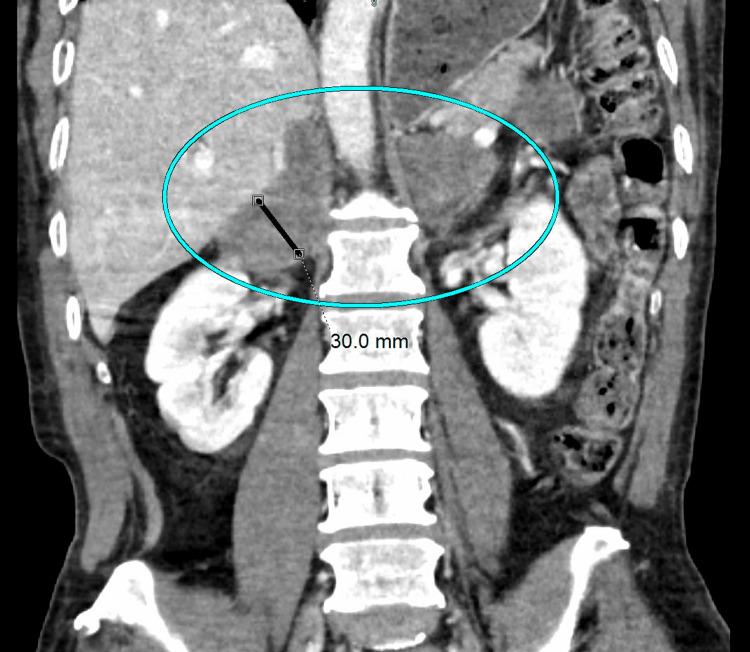

Histoplasmosis, a fungal infection caused by the inhalation of conidia spores, has been shown to cause disseminated disease in immunocompromised individuals. Disseminated histoplasmosis manifests as multi-system involvement including pulmonary and/or neurological disease. Imaging findings, such as pulmonary focal infiltrates, cavitary nodules, mediastinal, and hilar lymphadenopathy, are common. Here, we report a rare case of disseminated histoplasmosis in a 58-year-old immunocompetent male with no occupational exposure. This patient presented with primary adrenal insufficiency, and a subsequent CT-guided biopsy of the adrenal gland was performed and revealed numerous spores containing . This patient also suffered from numerous pulmonary and neurological derangements, which are likely sequelae of the disseminated fungal infection. Ultimately, the patient succumbed to their illness and died. Preventing such outcomes relies on early detection and prompt management, which are crucial in treating disseminated histoplasmosis. Increased awareness of atypical presentations can enhance patient outcomes and alleviate the impact of this severe fungal infection. This case not only underscores the importance of considering disseminated histoplasmosis in an immunocompetent patient presenting with unexplained weight loss and adrenal insufficiency but also contributes to the limited literature on disseminated histoplasmosis in immunocompetent individuals.

组织胞浆菌病是一种因吸入分生孢子而引起的真菌感染,已被证明会在免疫功能低下的个体中引发播散性疾病。播散性组织胞浆菌病表现为多系统受累,包括肺部和/或神经系统疾病。影像学表现,如肺部局灶性浸润、空洞性结节、纵隔和肺门淋巴结肿大,较为常见。在此,我们报告一例罕见的播散性组织胞浆菌病病例,患者为一名58岁免疫功能正常的男性,无职业暴露史。该患者出现原发性肾上腺功能不全,随后进行了CT引导下的肾上腺活检,结果显示有大量含孢子的组织。该患者还患有多种肺部和神经系统紊乱,这可能是播散性真菌感染的后遗症。最终,患者因病死亡。预防此类后果依赖于早期发现和及时治疗,这对治疗播散性组织胞浆菌病至关重要。提高对非典型表现的认识可以改善患者预后,减轻这种严重真菌感染的影响。该病例不仅强调了在出现不明原因体重减轻和肾上腺功能不全的免疫功能正常患者中考虑播散性组织胞浆菌病的重要性,也为免疫功能正常个体播散性组织胞浆菌病的有限文献增添了内容。